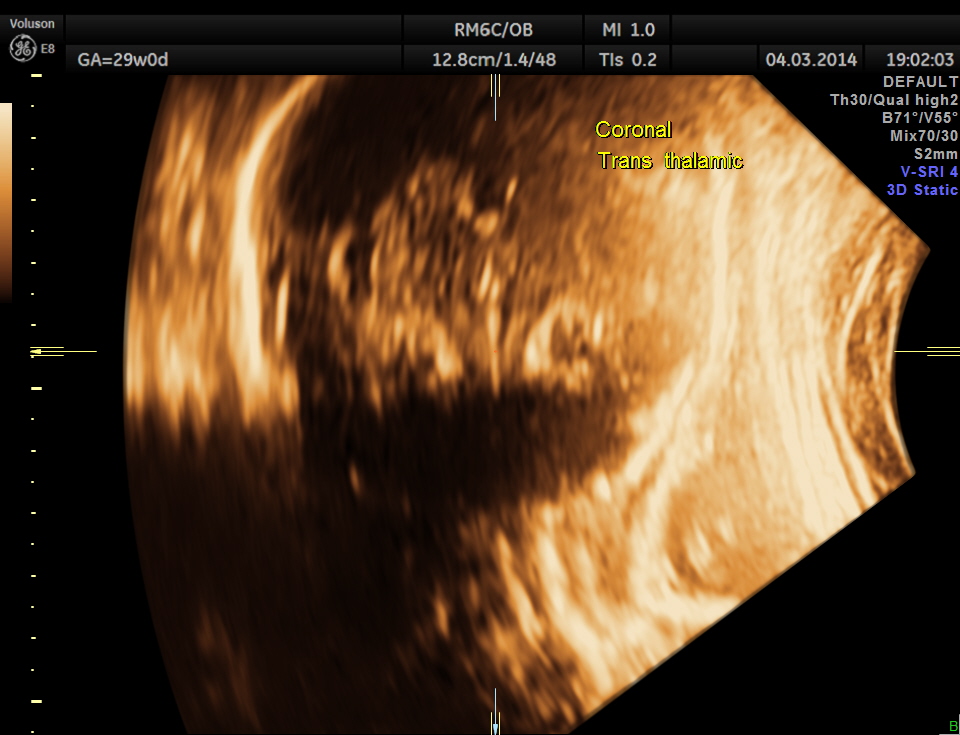

In this patient no other associated anomaly could be made out and so she was re assured ; She came for a review 1 month later.

The unilateral choroid plexus cyst could not be seen now. No other anomaly was made out.